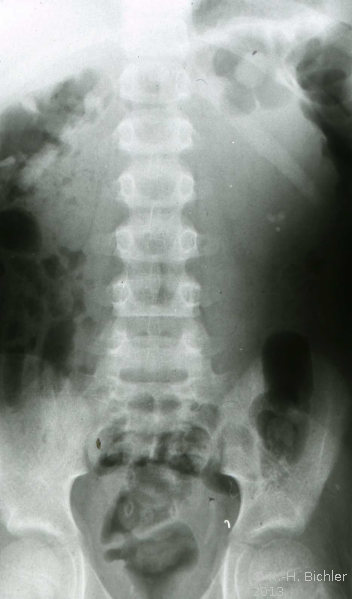

Bei dem 8-jährigen Jungen waren Schmerzen im linken Oberbauch sowie rezidivierende Harnwegsinfekte Ursachen für die Abklärung. sonographisch und röntgenologisch fanden sich Nierenkelchkonkremente in einer Harnstaaungsniere (Abbildungen 21,22,23). Bei der retrograden Sondierung ergab sich ein deutlicher Widerstand in Höhe des Ureterabgangs. Die Freilegung zeigte eine aberrierende Arterie als Abflusshindernis. Nach Durchtrennung des Harnleiters Eröffnung des Nierenbeckens zur Steinentfernung und Abgangsplastik des vorgelagerten Harnleiters. Normalisierung der Abflussverhältnisse.